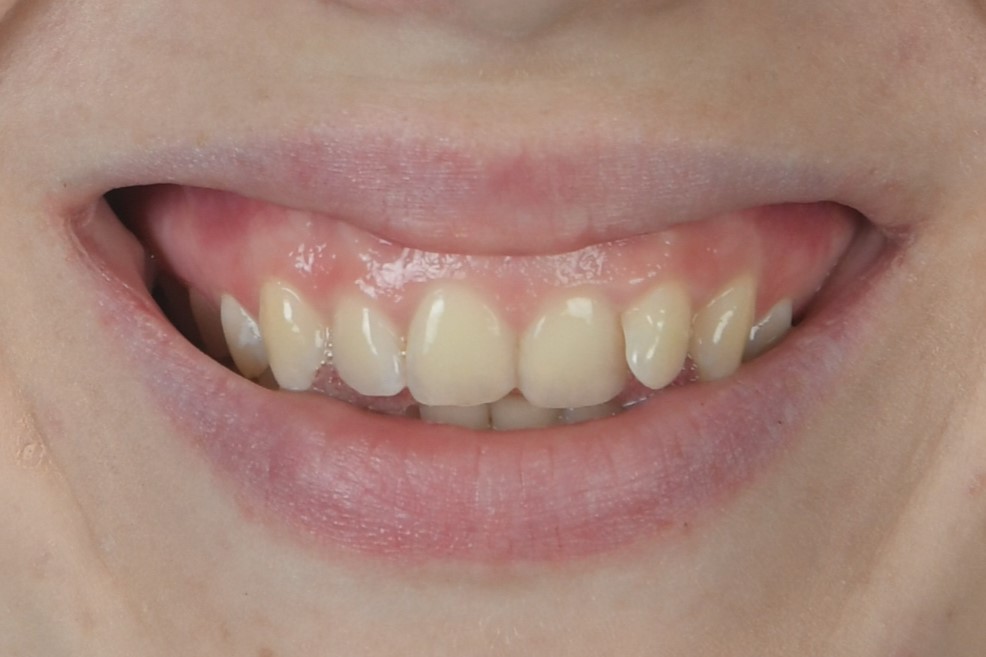

"Твоя улыбка КРАСИВАЯ и не нужно прикрывать рот рукой. Вот ради этого ощущения и стоило носить брекеты!" Дарья

Стеснялась улыбаться, потому что один зуб был как будто спрятан назад и казалось, что его нет. Сейчас я счастлива, что могу уверенно улыбаться и моя улыбка мне нравится!

Мне не нравилась моя улыбка и я постоянно испытывала смущение. Очень рада, что решилась на ортодонтическое лечение!

Я такая счастливая!!! Могу улыбаться, не стесняясь!! Спасибо моему ортодонту Ольге Валерьевне и команде клиники ОК!!

Мне так хотелось улыбаться красивой улыбкой, но я видела только свои острые клыки. Хочу сказать огромное спасибо за свою новую улыбку, потому что теперь я ощущаю гармонию, когда вижу себя в зеркале.

Когда стесняешься улыбаться, то и радости в жизни кажется не так много. Получив свою красивую улыбку, я постоянно теперь нахожу поводы для радости!